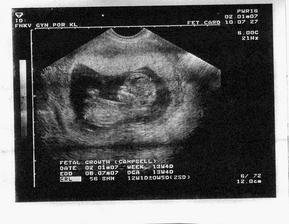

Honzíček 2.7.2007

Někdy kolem 12. července by se nám mělo narodit naše první miminko. Všichni se už moc těšíme :o)

Podle ultrazvuku ve 20.tt by to měl být chlapeček.

Nakonec přišel Honzíček na svět už 2.7. 2007 v 11:15 císařským řezem. Měřil 50 cm a vážil 3320 g.